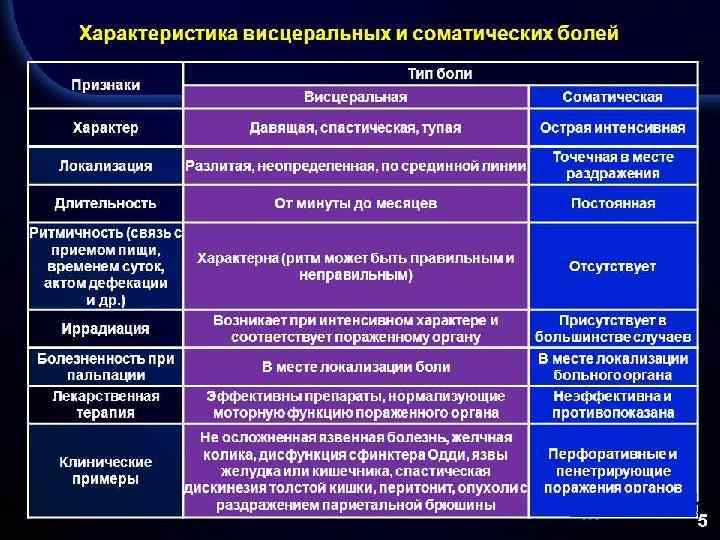

Клинические признаки 1. Выраженный абдоминальный болевой синдром Висцеральная боль Соматическая боль Иррадиирущая боль 2. Напряжение мышц передней стенки брюшной полости Локальное Генерализованное 3. Тошнота Рвота Желудочным содержимым Кишечным содержимым Кровью/ «кофейной» гущей 4. Нарушение моторики кишечника Запор Вздутие Интоксикация 5. Анемия Постгеморрагическая Железодефицитная 6. Шок Септический Травматический Геморрагический